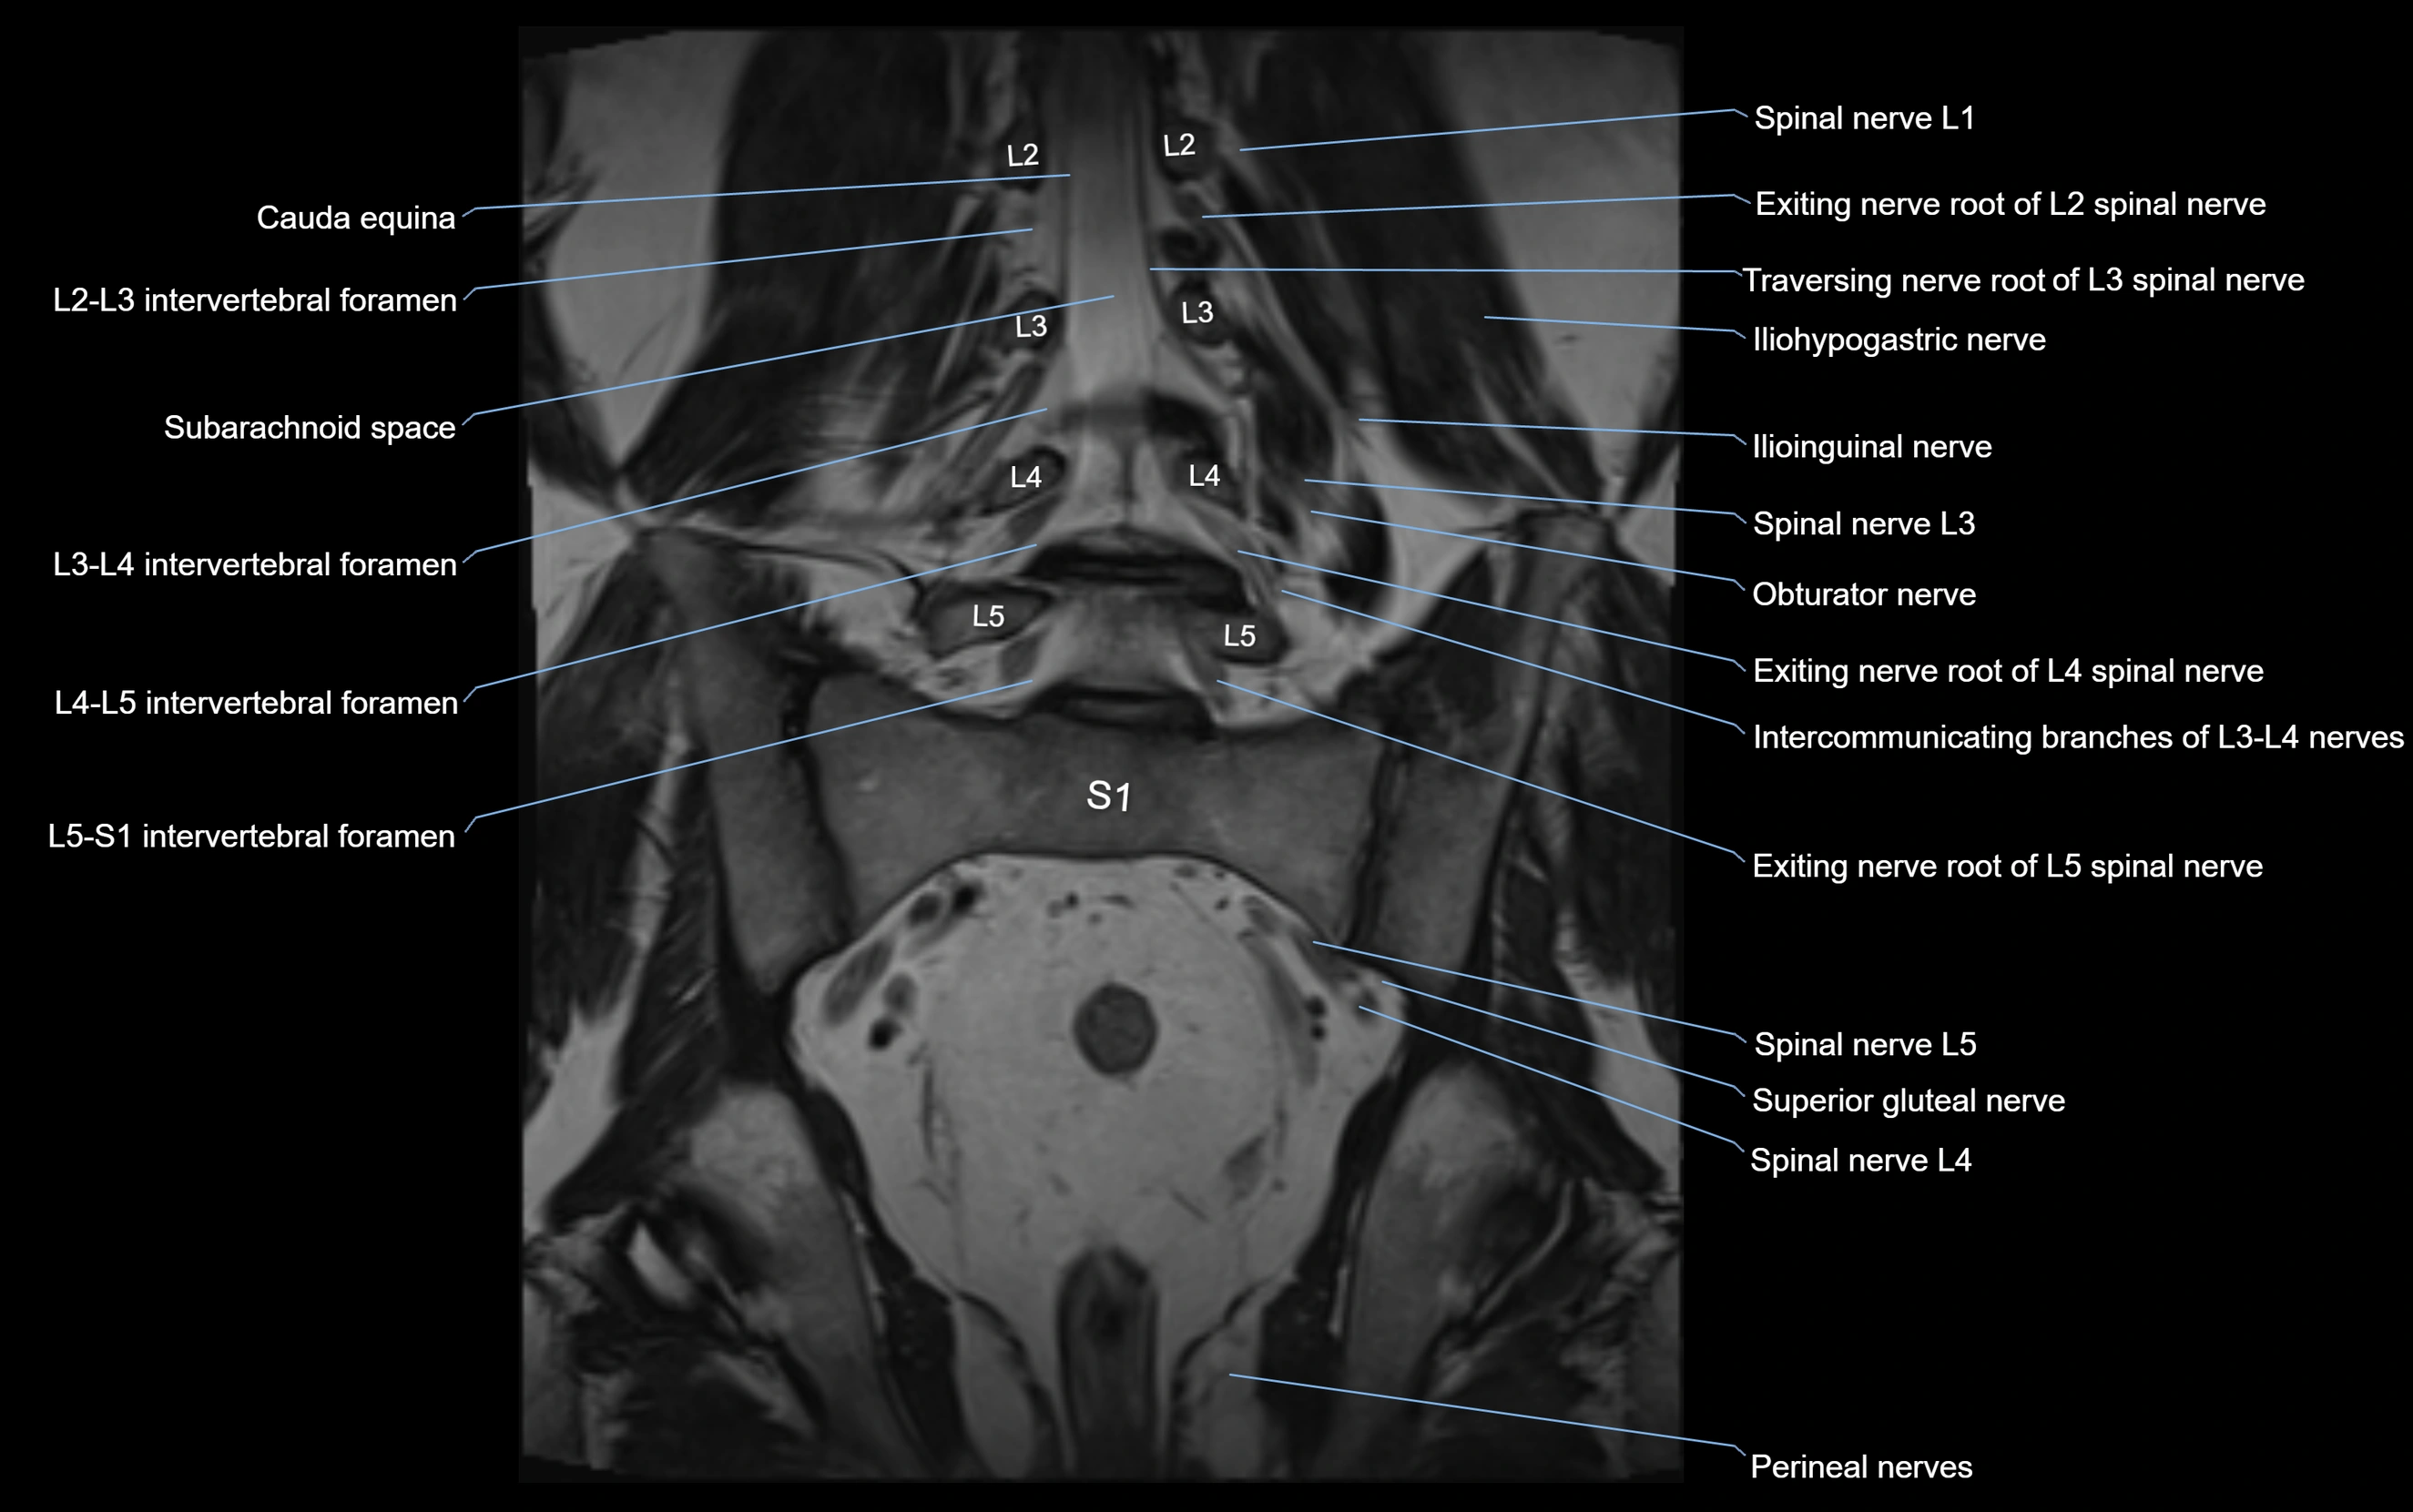

MRI image

image